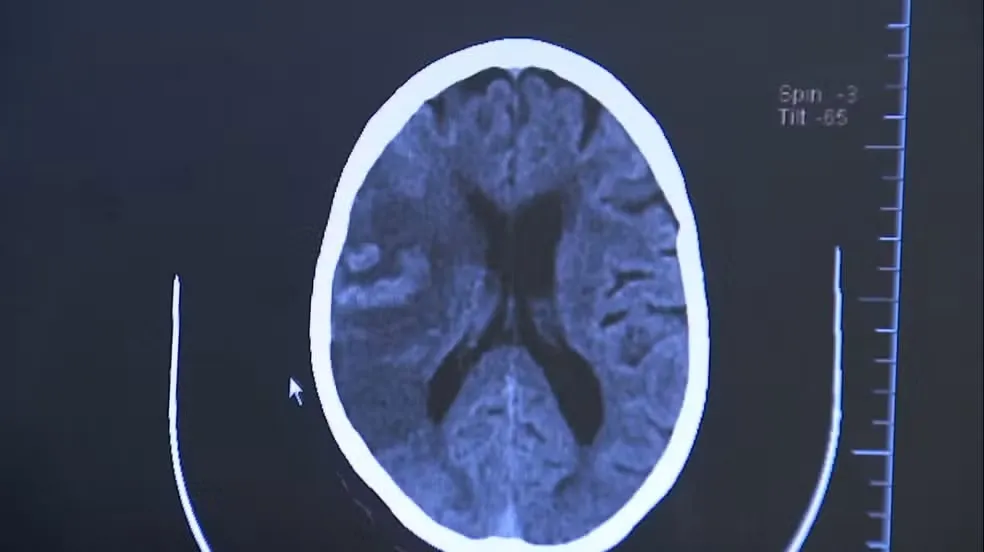

CAFÉ PODE REDUZIR A CHANCE DE DEMÊNCIA, DIZ ESTUDO

CAFEZINHO DO BEM 25/02/2026 - 10h03

CAFÉ PODE REDUZIR A CHANCE DE DEMÊNCIA, DIZ ESTUDO Beber de duas a três xícaras de café ou chá cafeinado por dia pode reduzir em cerca de 20% o risco de demência, aponta um estudo que acompanhou mais de 130 mil pessoas por 40 anos.